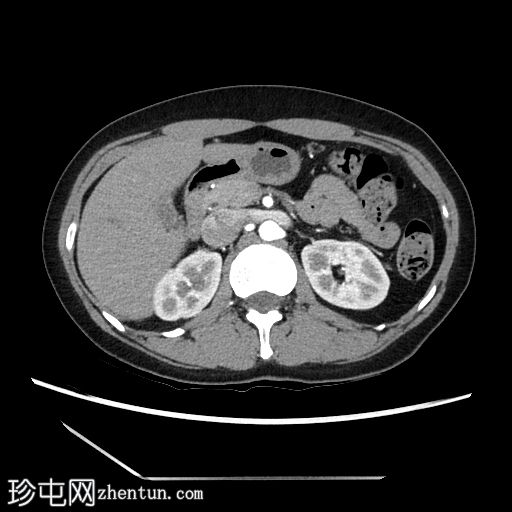

2.jpg

轴向C+期

动脉期

在轴向、冠状面和矢状面上均可见肝5/6段病变。动脉期可见周围结节状强化,门静脉期可见进行性向心性充盈,延迟期亦持续存在。这些表现为肝血管瘤的特征性表现。

然而,目前的CT扫描显示动脉期呈周围结节性强化,门静脉期呈进行性向心性充盈,且延迟成像后仍持续存在。这些特征是肝血管瘤的特征。未发现其他肝脏病变。